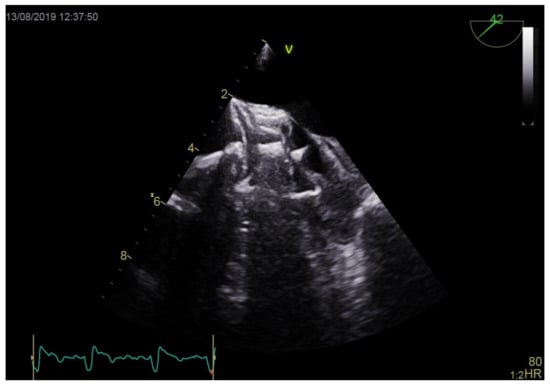

3.4. Percutaneous Closure of Left Atrial Appendage with Thrombus Procedure

| LAA thrombus location (portion) ½ proximal ½ distal | 0 (0.0%) 17 (100%) |

| Thrombus burden area within LAA/LAA area (%) | 22.1 ± 5.6 |